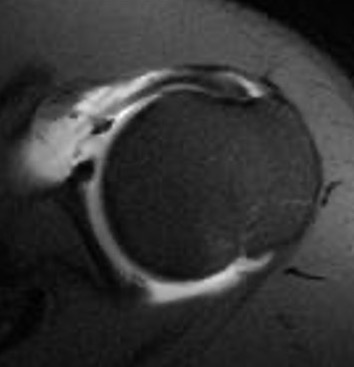

Anterior instability but no anterior labral tear on MRI

Differential diagnosis

| HAGL | Capsular teearing | Anterior capsular stretching |

|---|---|---|

| IGHL avulsed anteriorly from humeral insertion | Labrum intact, but anterior capsule torn in two |

Labrum and capsule intact Capsule stretched Patient has ligamentous laxity but unidirectional anterior instability |

Intact labrum on MRI

Anterior labrum intact, evidence of capsule tearing + HAGL on MRI